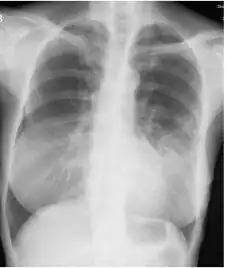

- Chest radiograph

- Image indicate bronchodilation, centrilobular granular shadow, and consolidation